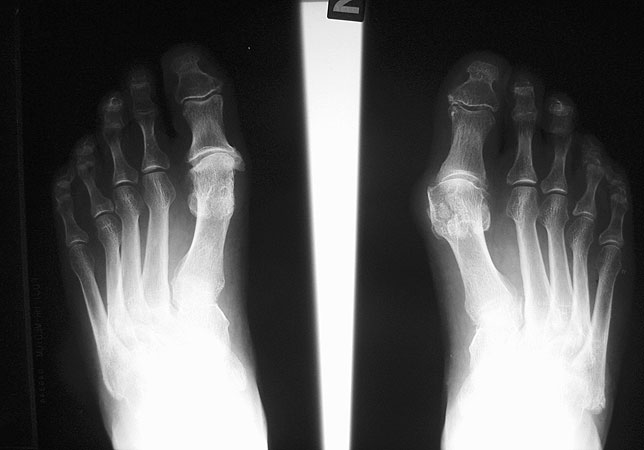

Röntgenbild 30 Jahre nach Brandes OP links zur OP Planung rechts.

Abbildung 6

Generell ist die subjektive Zufriedenheit der Patienten mit dieser Operationstechnik aber sehr hoch und die Komplikations- und Revisionsrate auch nach langer Zeit  im Vergleich zu konkurrierenden Verfahren gering 14. Auch sehen wir unverändert Patienten die 20-30 Jahre nach Primäreingriff zufrieden zur Operation der Gegenseite kommen (Abb. 6)